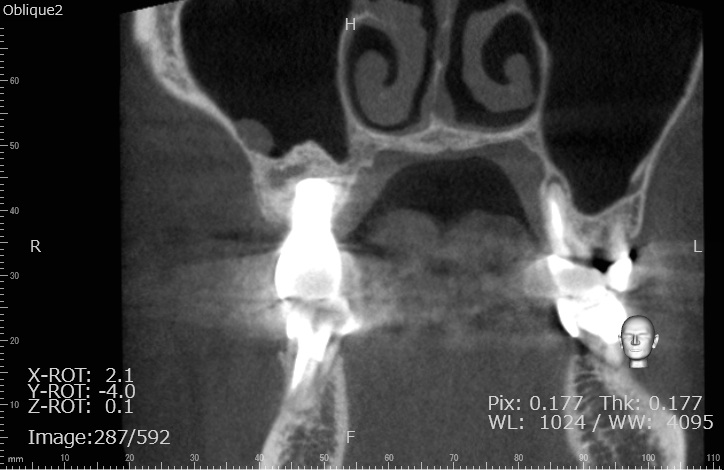

Case4

術前

術中

術後

| 治療名 | GBRとインプラントを行った症例 |

|---|---|

| 治療説明 | インプラントを埋入予定の部位において、骨の吸収が見られたため、インプラント埋入と同時に小規模な骨造成(GBR)を行いました。治癒期間を経て、最終的にセラミックの上部構造を装着し、自然な見た目としっかりとした噛み合わせを回復しました。 |

| 治療回数・期間 | 6ヶ月 |

| 副作用とリスク | インプラント治療は、入れ歯やブリッジに比べて治療期間が長くなる傾向があります。骨造成が必要な場合は、さらに治療期間が延びることがあります。 また、手術後には一時的な違和感や痛み、腫れ、出血などが生じる場合がありますが、通常は2日〜1週間ほどで落ち着きます。 |

| 料金(税込) | GBR〈小規模骨造成〉:110,000円 インプラント一次手術:220,000円 二次手術:55,000円 上部構造〈セラミック〉:165,000円 合計:550,000円 |